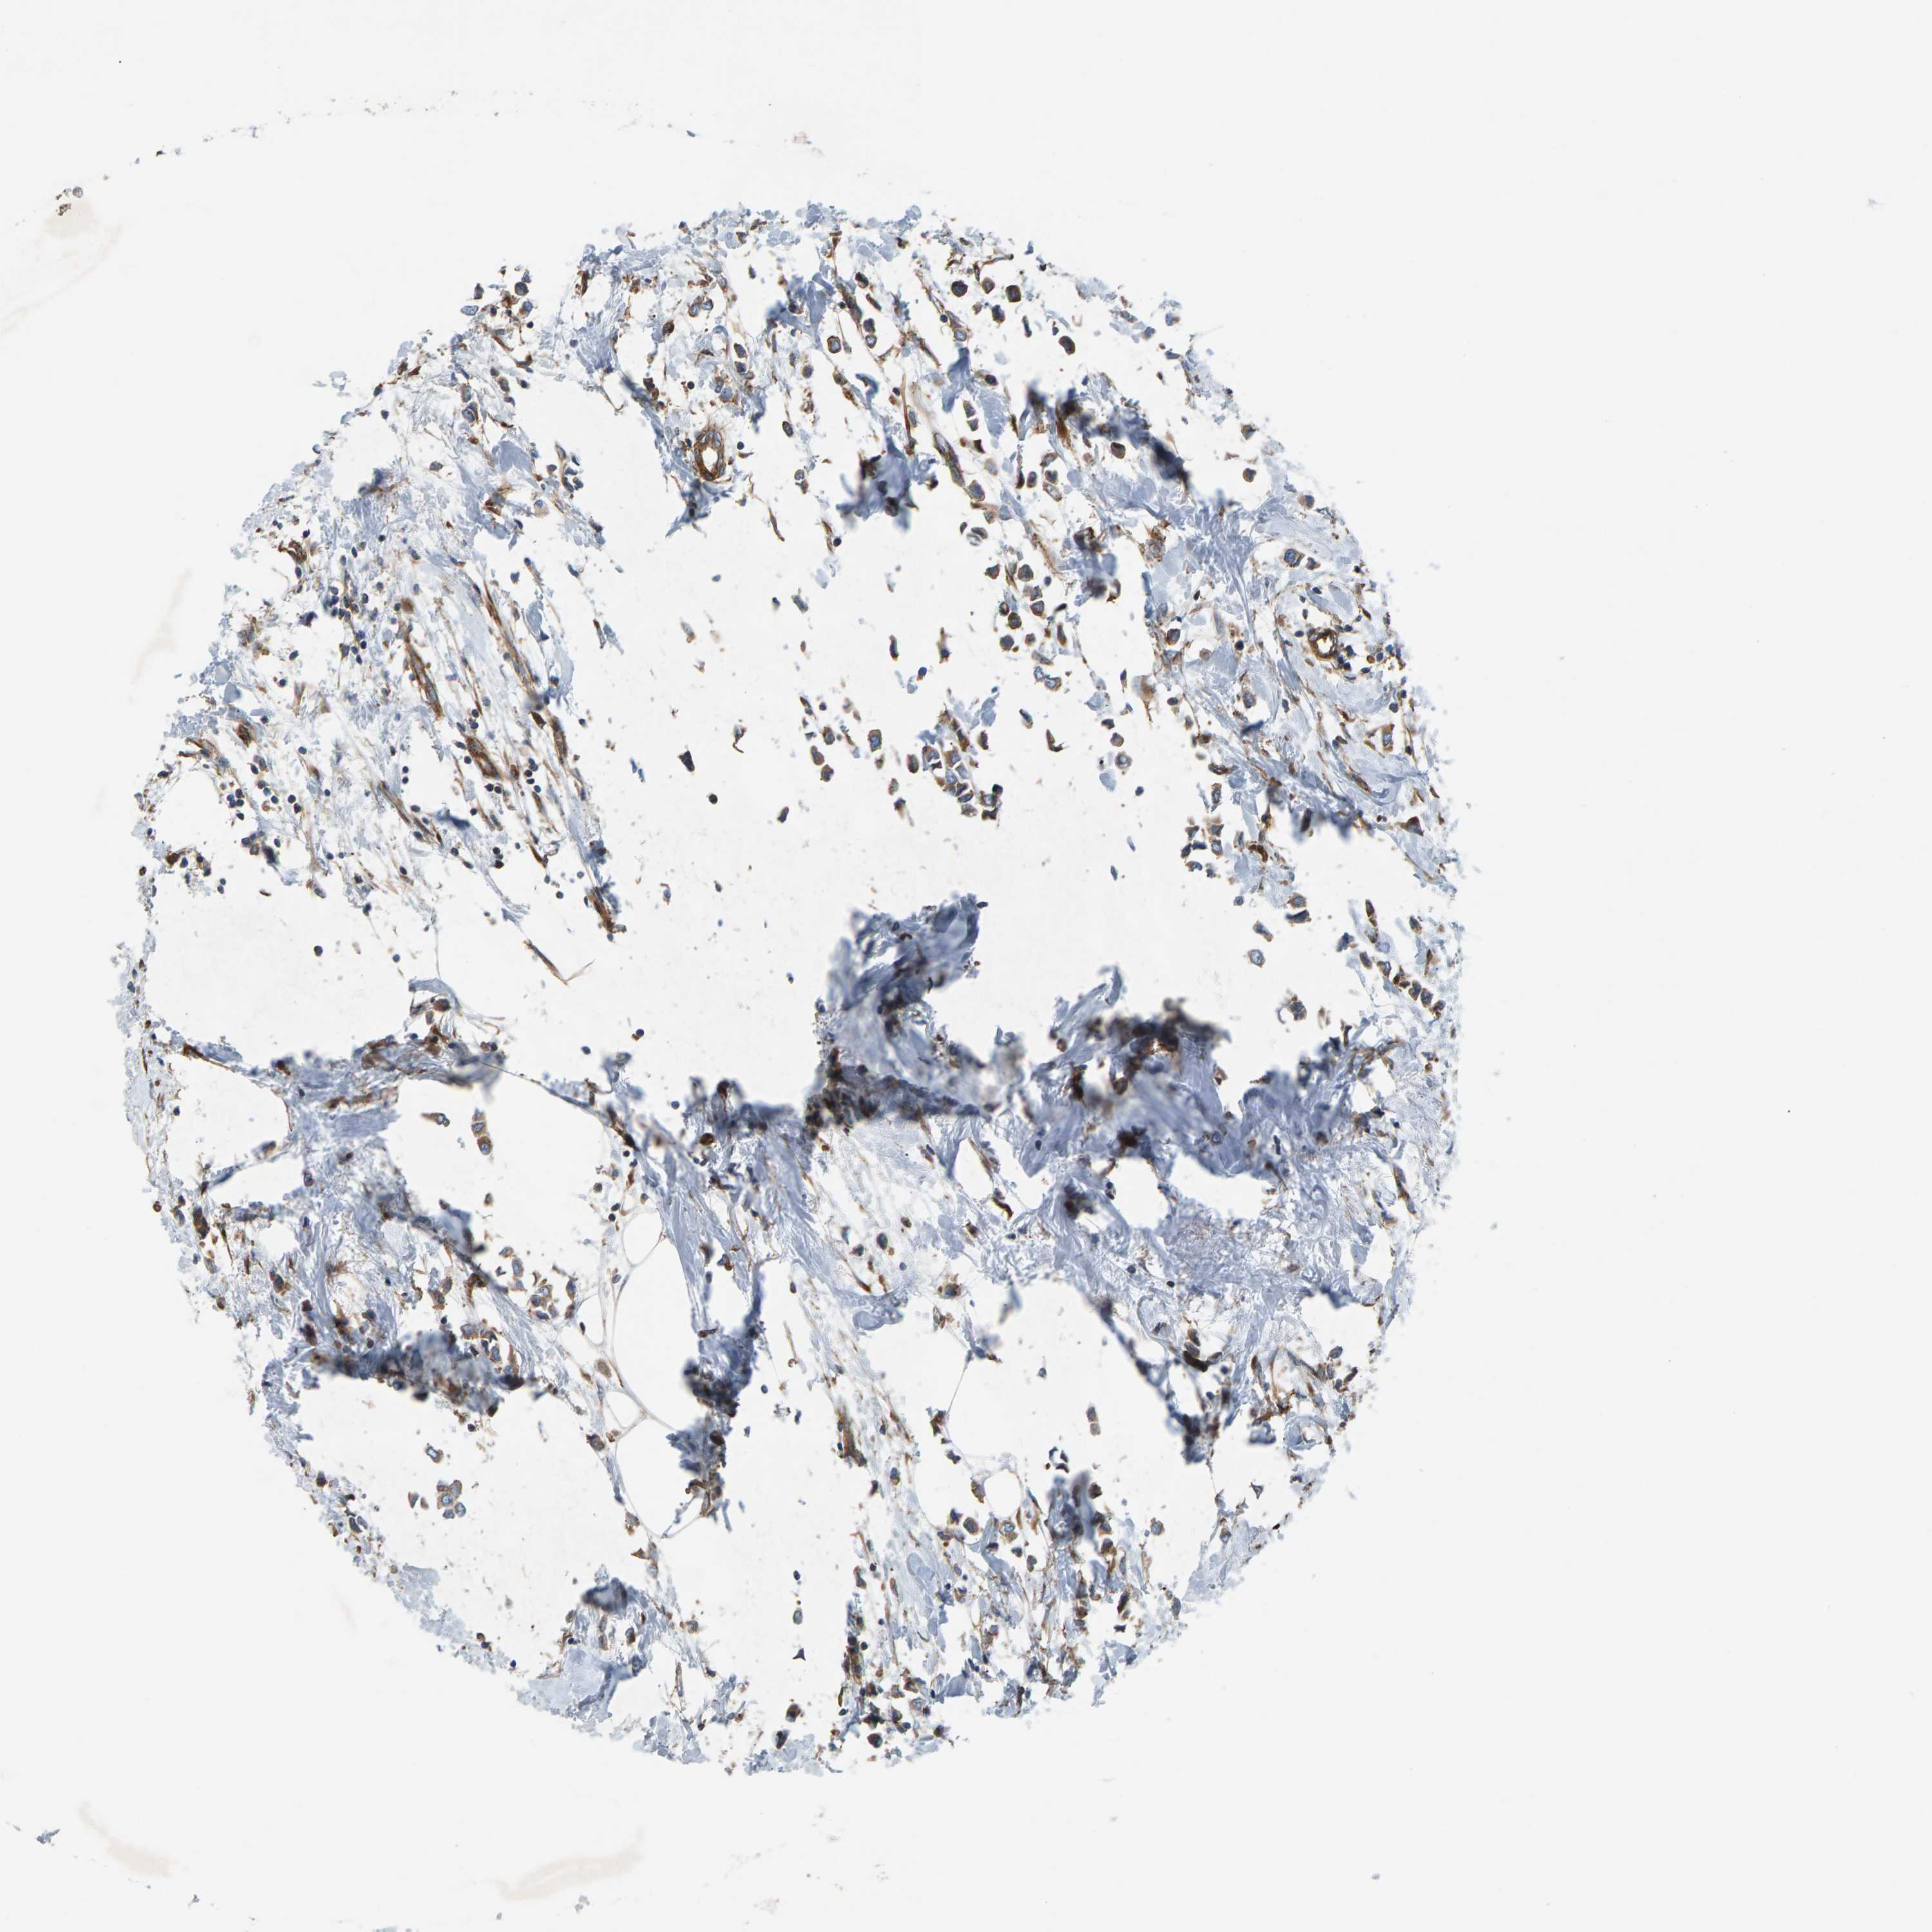

CANCER BREAST CANCER Show tissue menu

BRCA TCGA BRCA VALIDATION PROTEIN EXPRESSION

ANTIBODIES

AND

VALIDATION